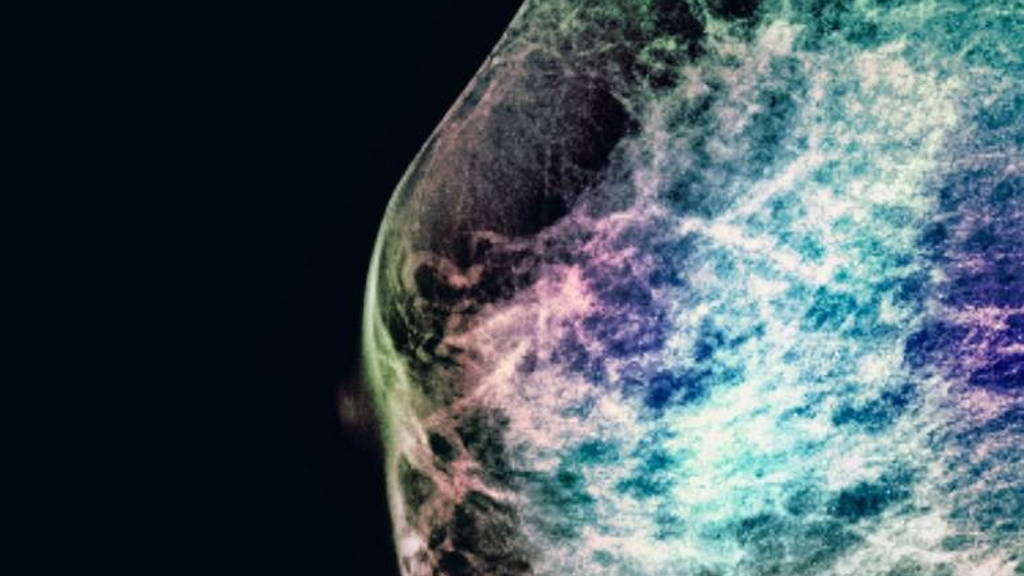

Computeralgoritmes zijn inmiddels in staat om menselijke pathologen te evenaren in het ontdekken van uitzaaiingen van borstkanker in lymfeklieren. Dit blijkt uit de CAMELYON16 challenge van het Radboudumc. Daarmee is het toepassen van kunstmatige intelligentie op een nieuw niveau gekomen bij het ondersteunen van medisch specialisten in het stellen van een diagnose.

In een publicatie in JAMA van 12 december schrijven onderzoekers dat zij voor het eerst laten zien dat algoritmes op basis van deep learning voldoende kwaliteit hebben om routinematige diagnoses te stellen op basis van weefselpreparaten. De techniek kan pathologen helpen om sneller en beter diagnoses te stellen.

Het Radboudumc organiseerde tussen november 2015 en november 2016 de CAMELYON16 challenge. Programmeurs kregen de kans om een computeralgoritme te maken dat zelfstandig een diagnose kan stellen op basis van aangeleverde pathologiebeelden. Het ging om het ontdekken van uitzaaiingen van borstkanker in lymfeklieren. Drieëntwintig onderzoeksgroepen wereldwijd gingen de uitdaging aan, waarvan de resultaten nu bekend zijn.

De deelnemers aan de challenge kregen de beschikking over 270 digitale preparaten waarvan al duidelijk was of, en waar, er uitzaaiingen te vinden waren. Op basis hiervan konden ze algoritmes programmeren en trainen in het herkennen van de uitzaaiingen. Vervolgens kregen de groepen 129 nieuwe preparaten waarmee ze het algoritme konden testen. De computer moesten preparaten met en zonder uitzaaiingen van elkaar onderscheiden. En in de preparaten met uitzaaiingen moesten de algoritmes aanwijzen waar deze precies zaten.